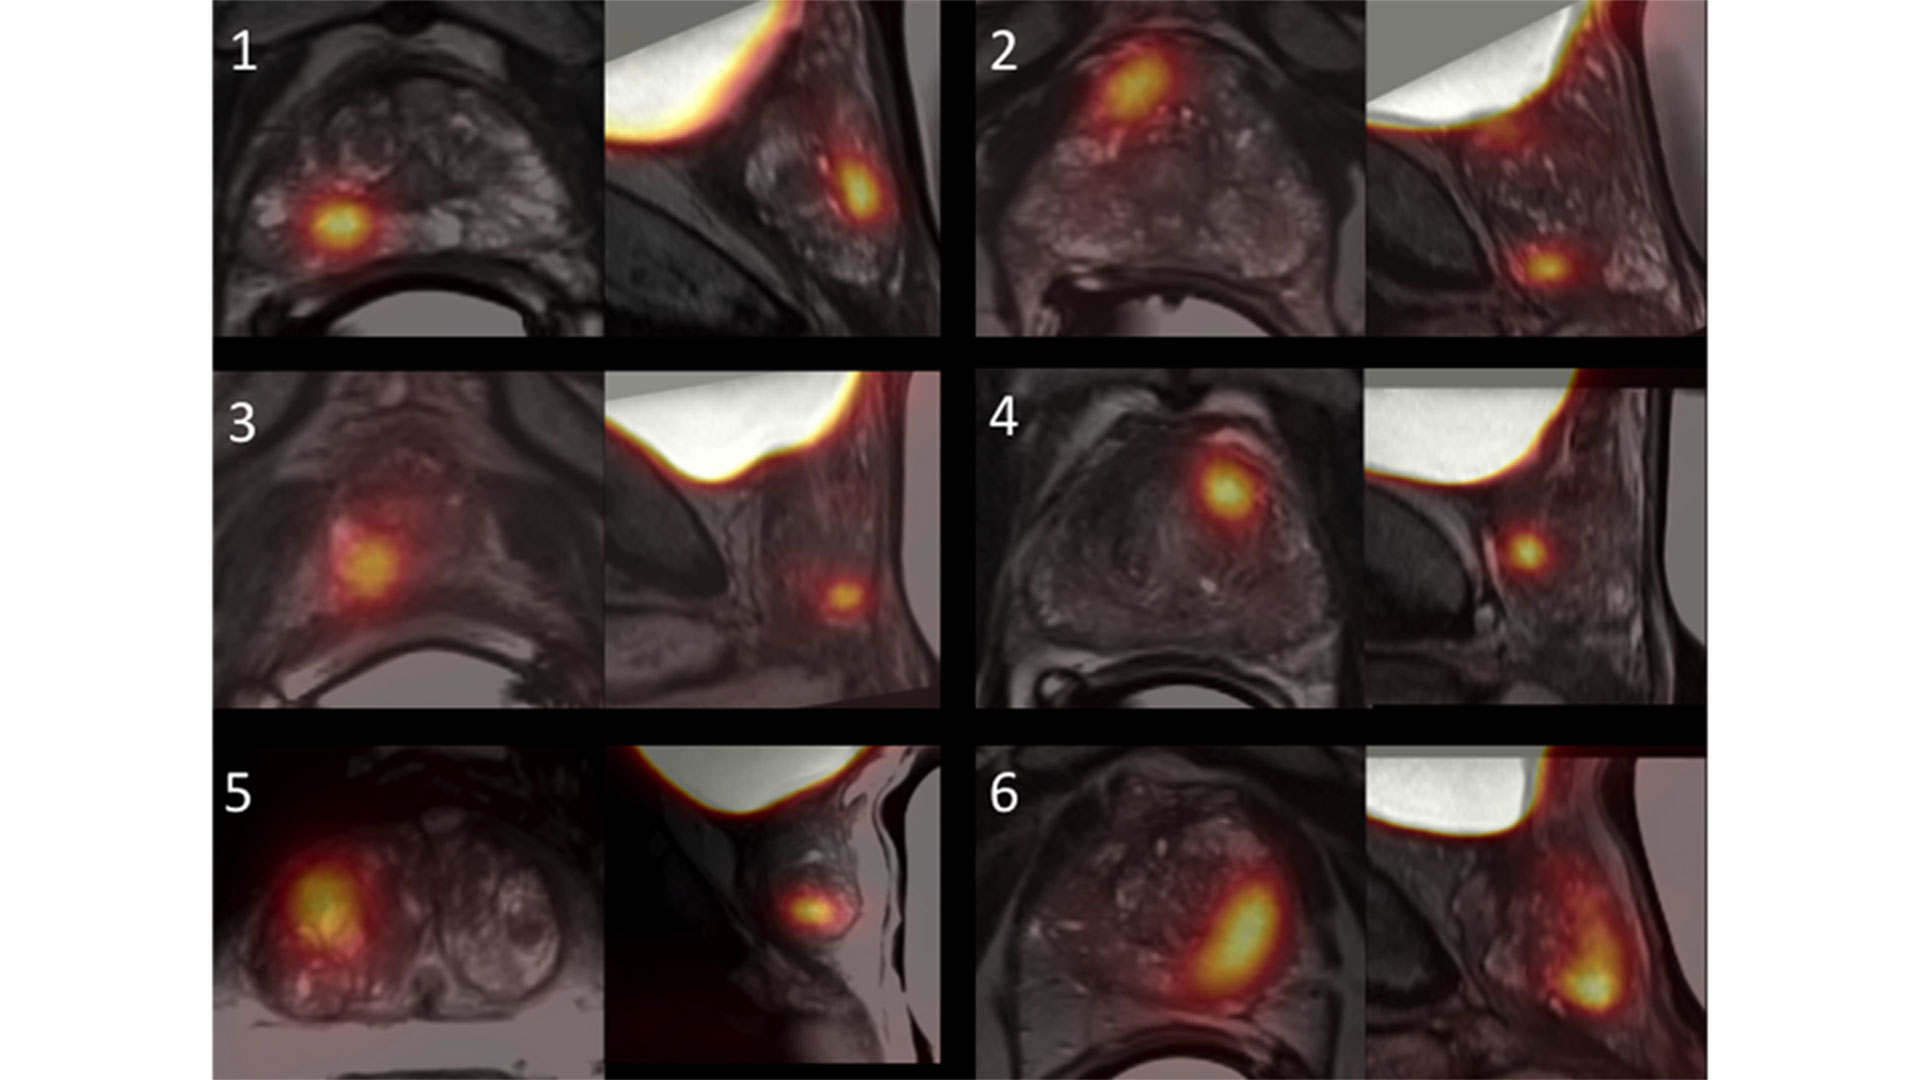

Scientists at Lawson are at the forefront of research that uses imaging agents that bind to a protein on the surface of prostate cancer cells called prostate specific membrane antigen (PSMA). Advanced imaging technology called PET/CT (positron emission tomography/computed tomography) and PET/MRI (magnetic resonance imaging) is then used to capture clear images of the location and extent of the cancer.

MRI and [18F]-DCFPyL PET images of six trial participants with prostate cancer.